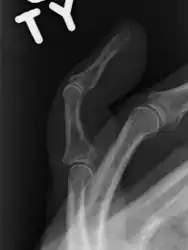

The diagnosis is generally based on symptoms and supported by X-rays.[3] The injury can be accompanied by swelling and ecchymosis.[6]

X-ray showing fracture at the insertion of the extensor tendon

A mallet finger without an associated fracture